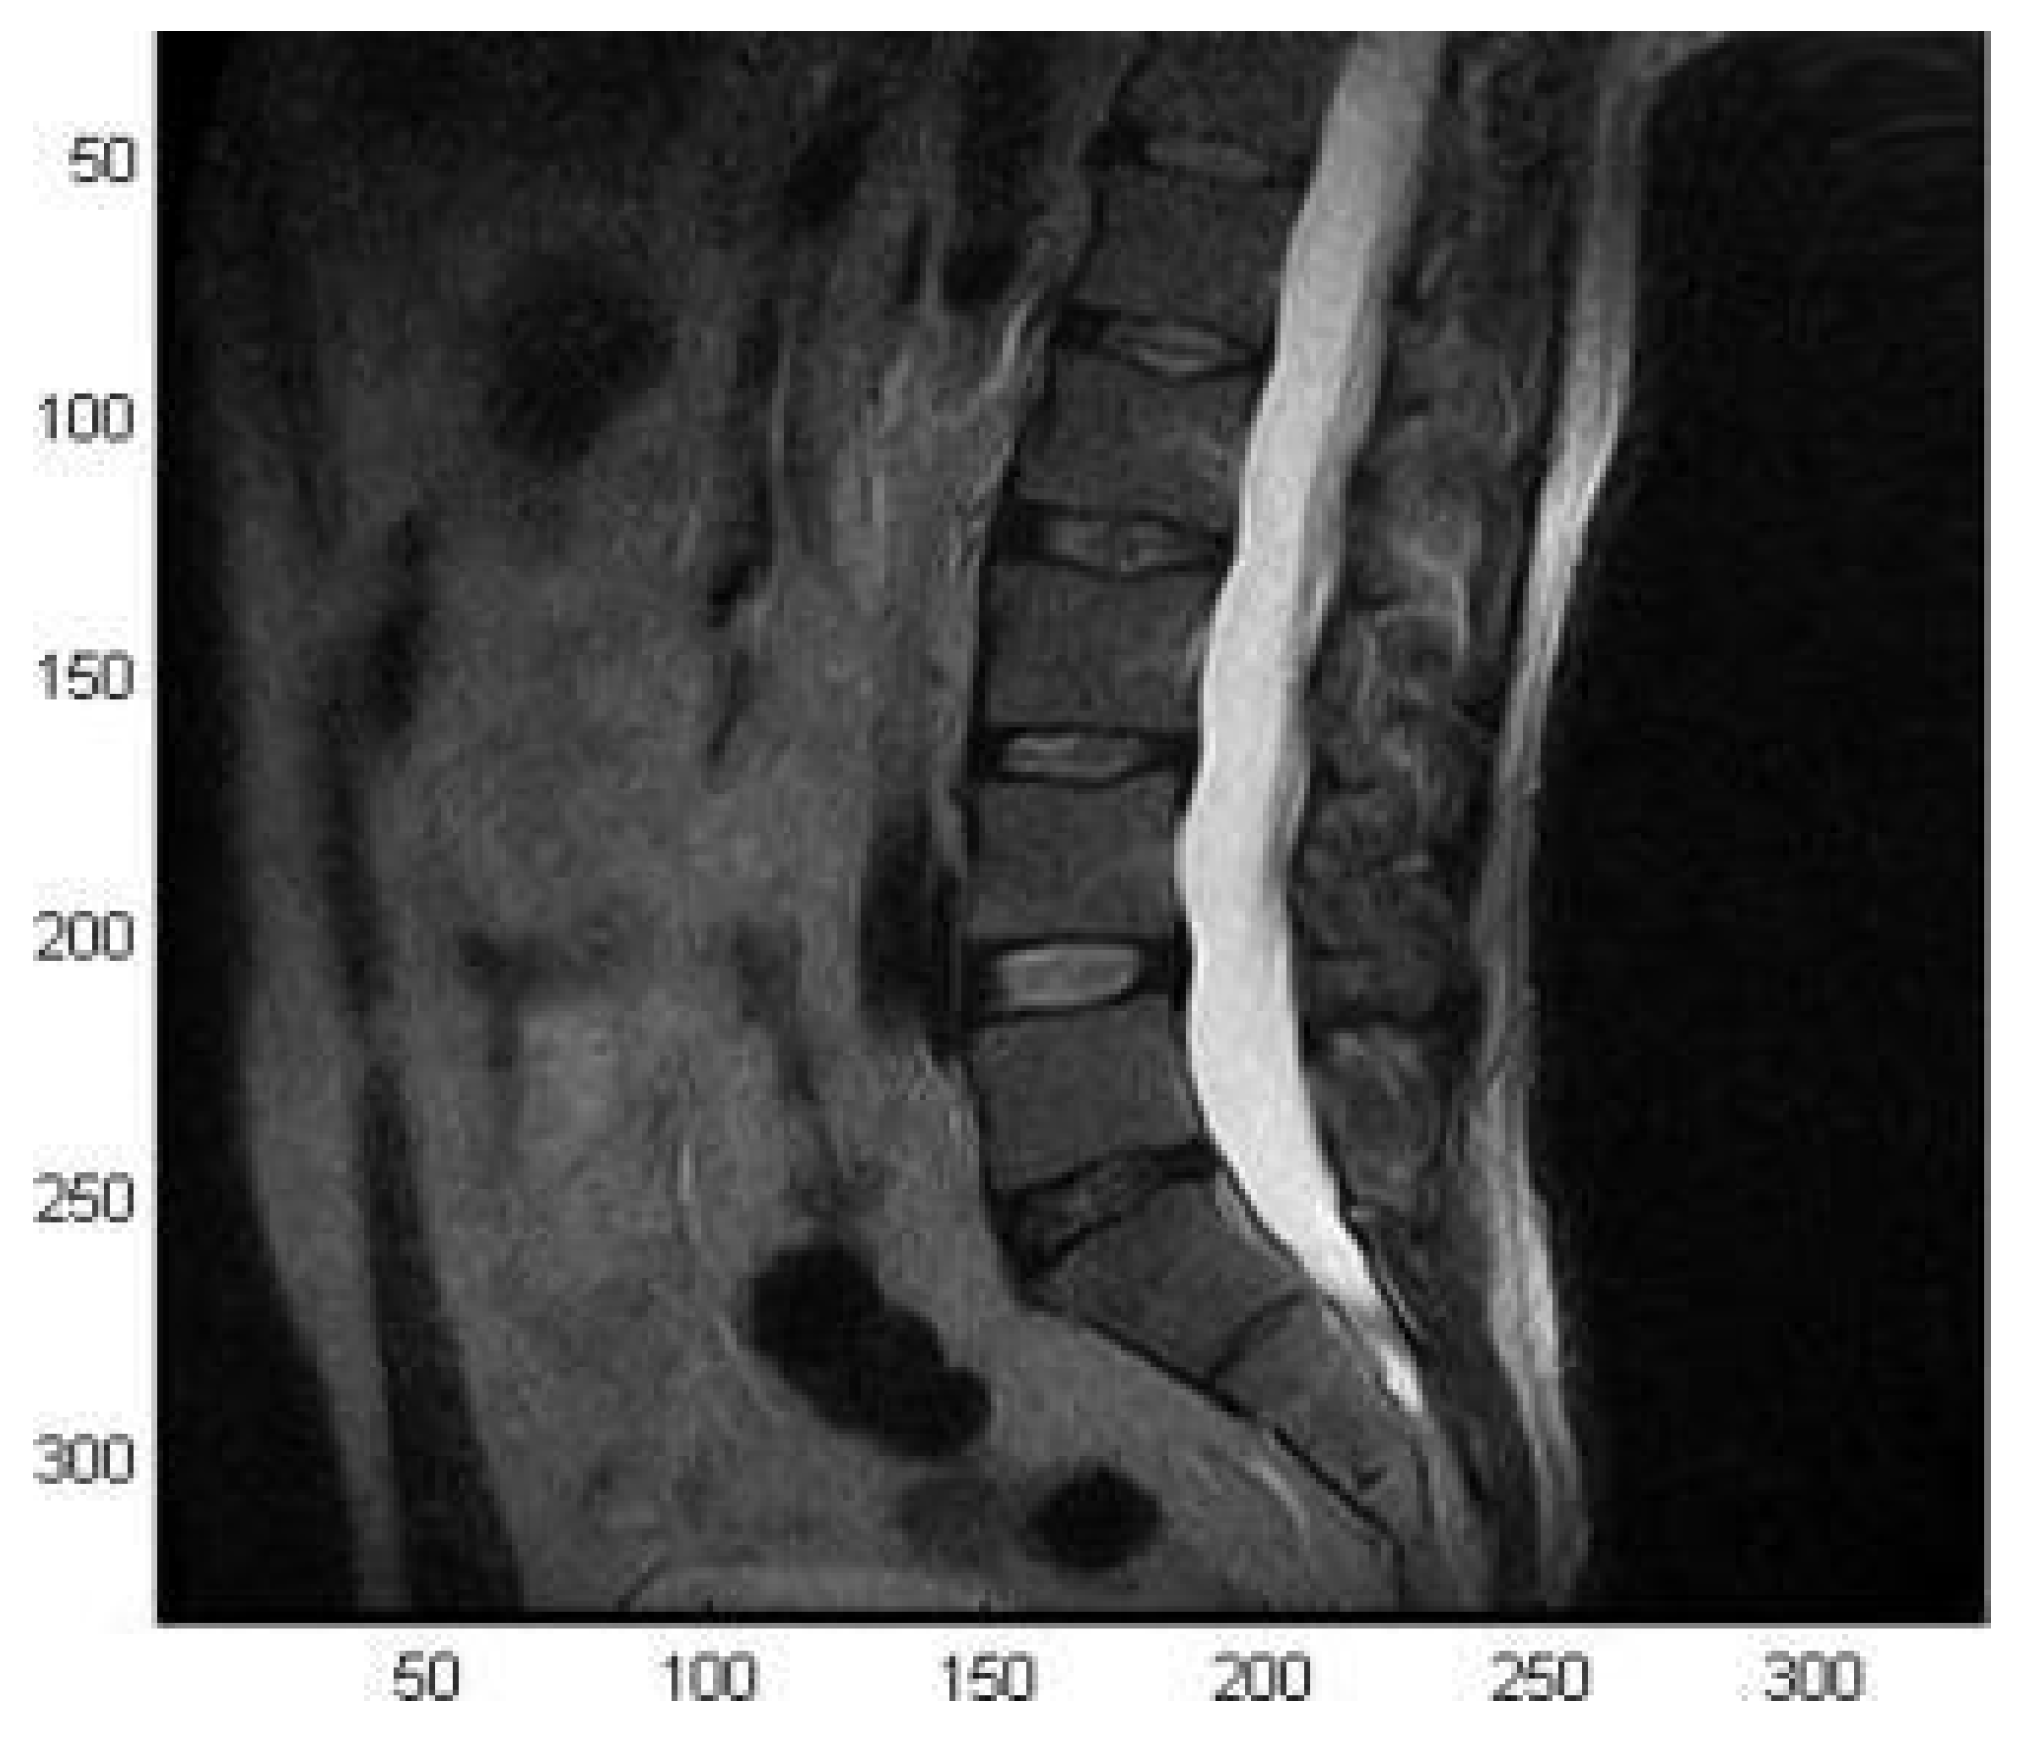

In particular, the presence of the shielding system did not significantly alter the decoupling between coil elements but determined a magnetic field intensity decrease while still preserving the homogeneity. Finally, the coil was used for the acquisitions of a volunteer’s spine (male, 45 years old, height: 185 cm, weight: 90 kg) with a spin-echo sequence (TE = 120 ms, TR = 3175 ms, FOV 30 × 30 cm2, matrix 256 × 192, slice thickness 4 mm, echo number 1, spacing between slices 5 mm, number of averages 1), showing its potential for providing high-quality images (Figure 7).

Figure 7.

MR image of the spinal column of a volunteer (sagittal view) acquired with the spine volume coil. Reprinted from [42].